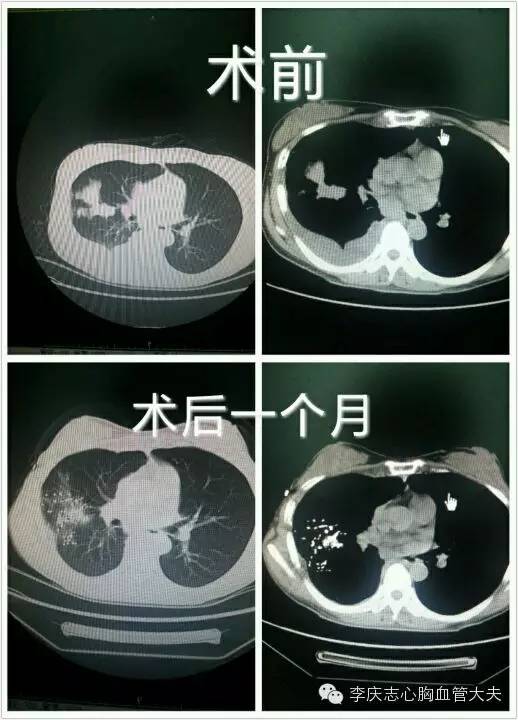

典型病例1: 张女士,47岁,发现肺癌时已出现胸膜转移、恶性胸腔积液,属于“不能行根治手术”的病人,行肺癌粒子植入后一个月,肿物明显缩小,恶性胸腔积液消失。